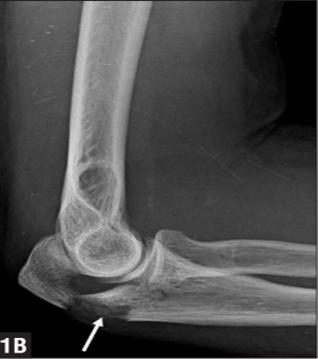

Las luxaciones anteriores de codo están asociadas a fracturas de olécranon (lesión de Hume). El manejo es quirúrgico, siendo el cerclaje con alambre el procedimiento de elección por la alta probabilidad de desplazamiento del fragmento roto.

El manejo es ortopédico mediante reducción, inmovilización en 90° y rehabilitación temprana. En caso se confirme una fractura de olécranon, se debe tratar de forma quirúrgica e incluye cerclaje más alambre en el olécranon. (ENAM 2019-A)